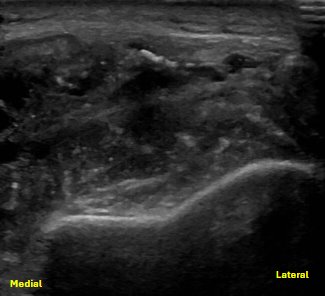

Unlabeled long axis view of the posterior elbow evaluating the region of the distal triceps insertion, with probe compression

Redemonstration of the distal tendon rupture, now with probe compression of the olecranon bursa and hematoma/seroma. Here, the posterior fat pad and distal humerus are labeled.

Unlabeled long axis view of the posterior elbow evaluating the region of the distal triceps insertion.